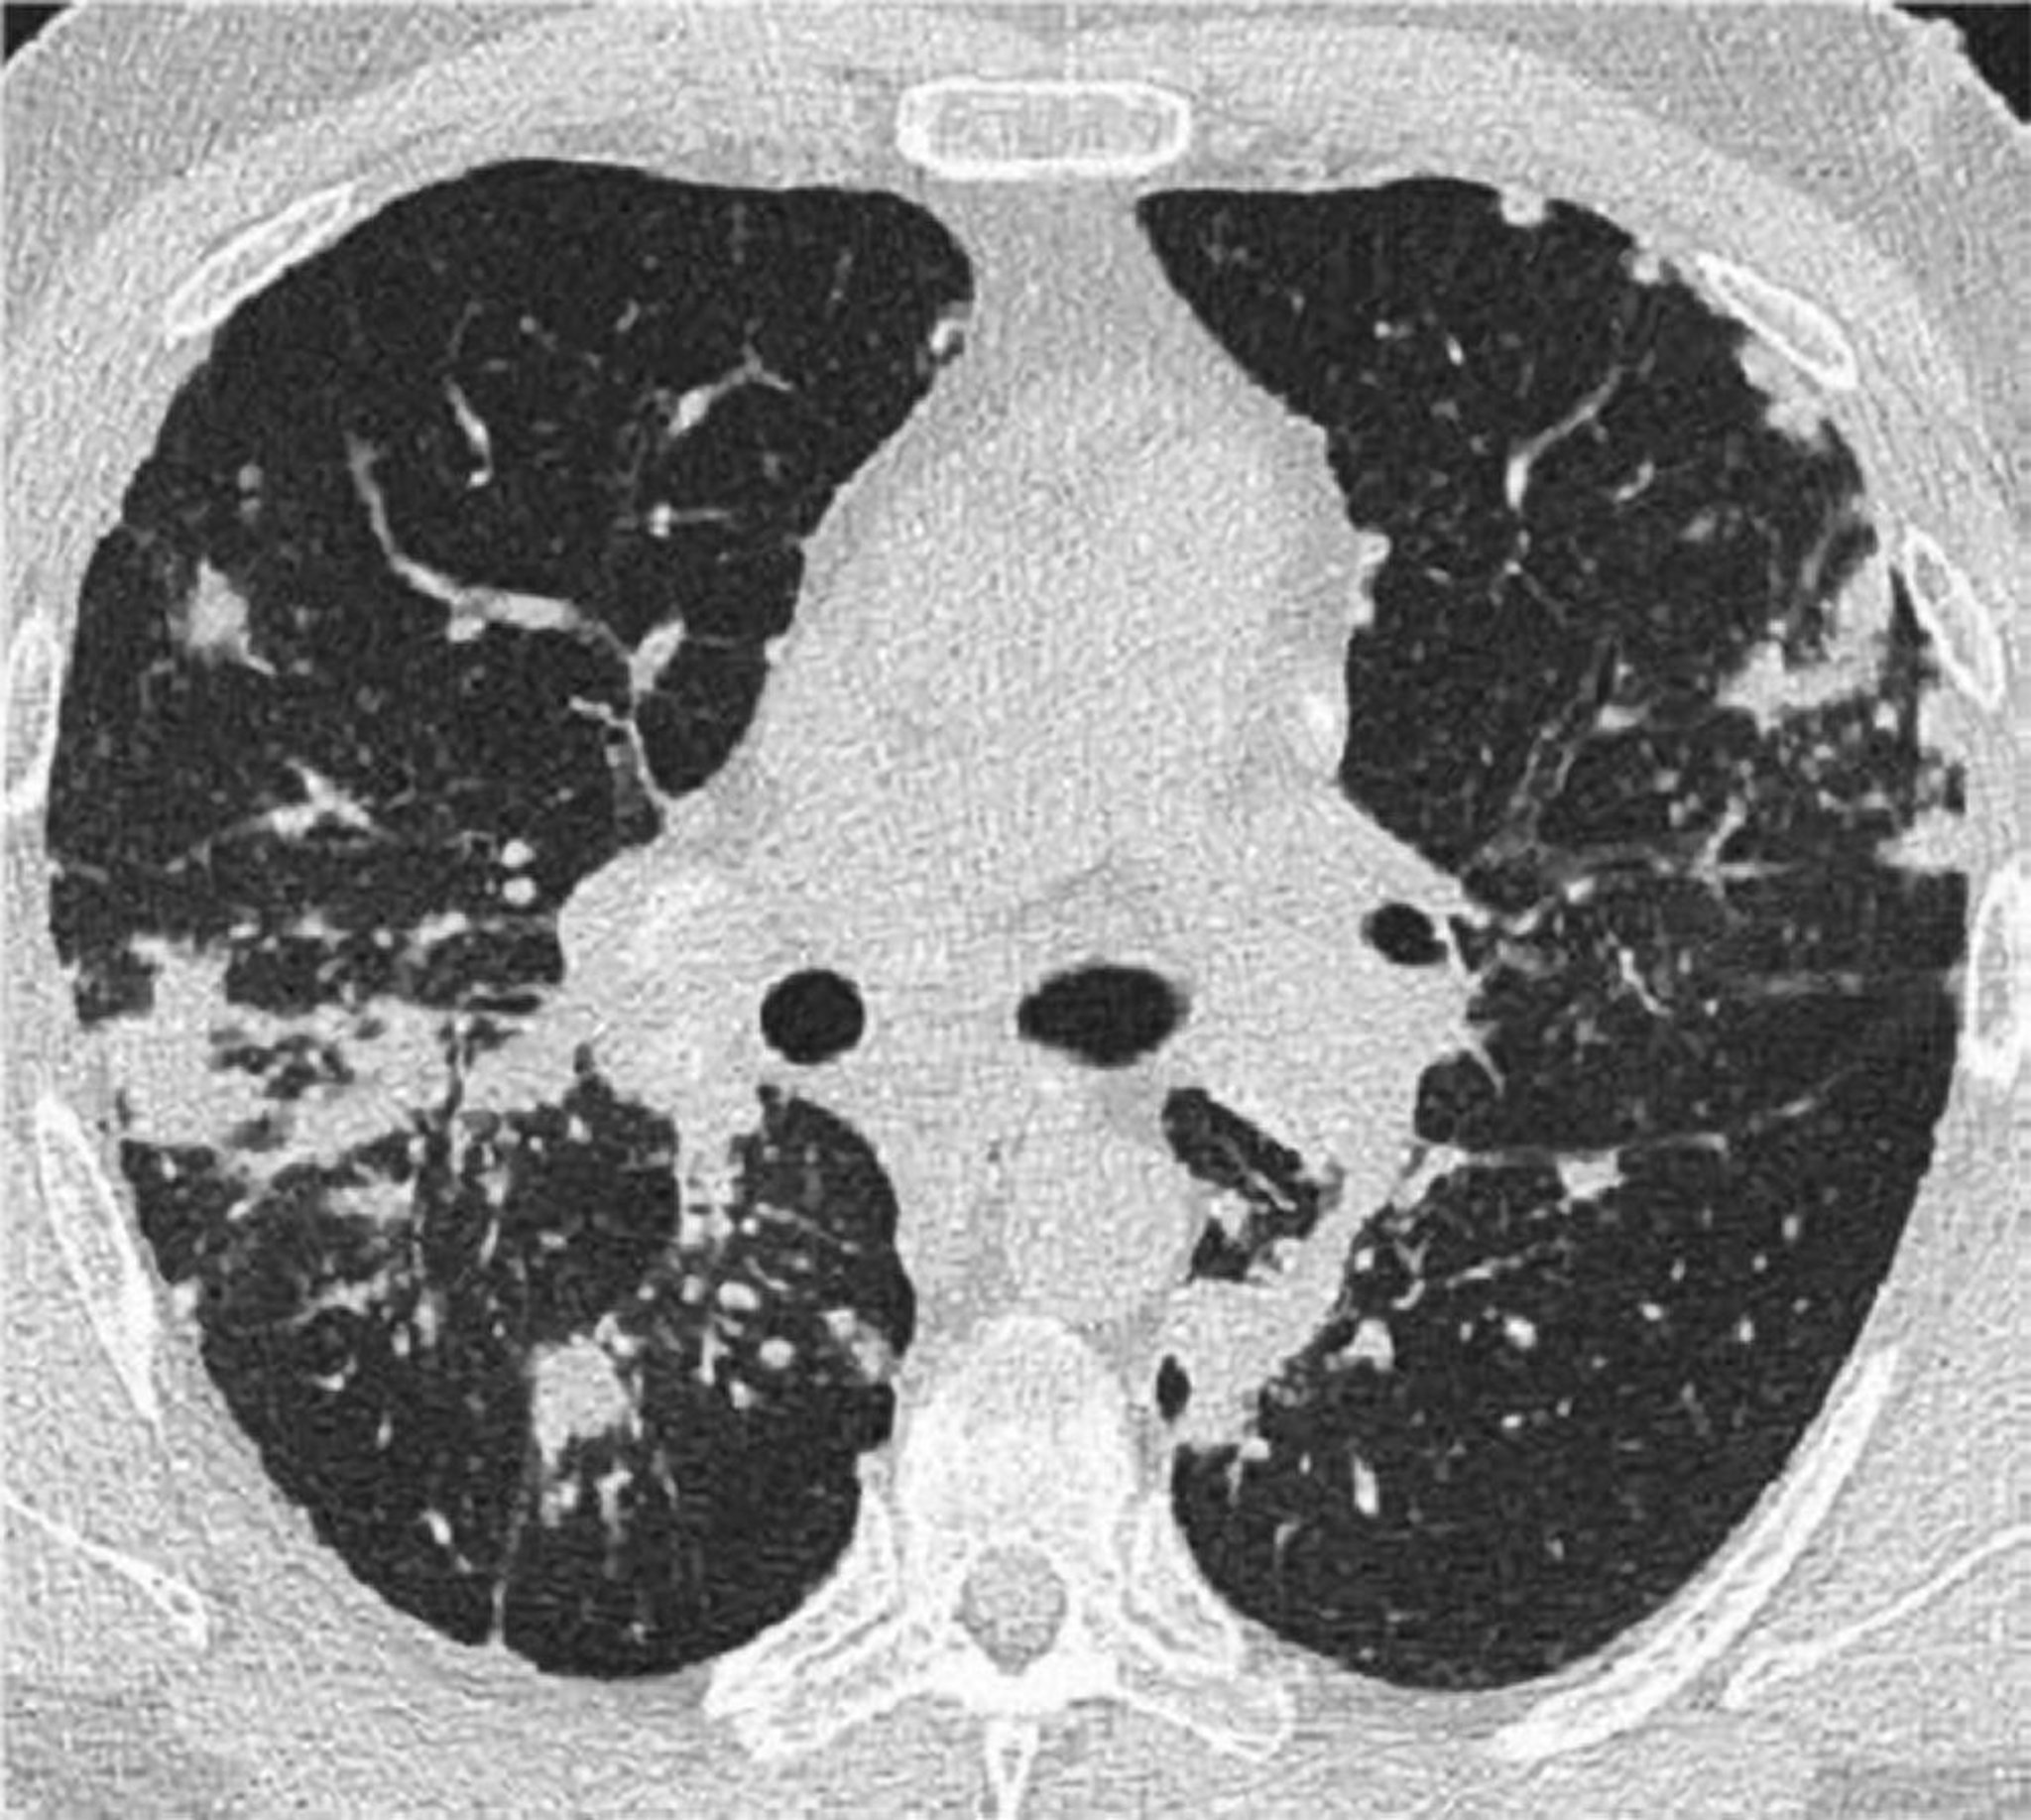

TDM thoracique d'une sarcoïdose pulmonaire

Cette TDM à haute résolution du thorax d'un patient atteint de sarcoïdose pulmonaire montre un épaississement des faisceaux bronchovasculaires et un perlage des septa interlobulaires.

Image courtesy of Birendra P. Sah, MD, FCCP.